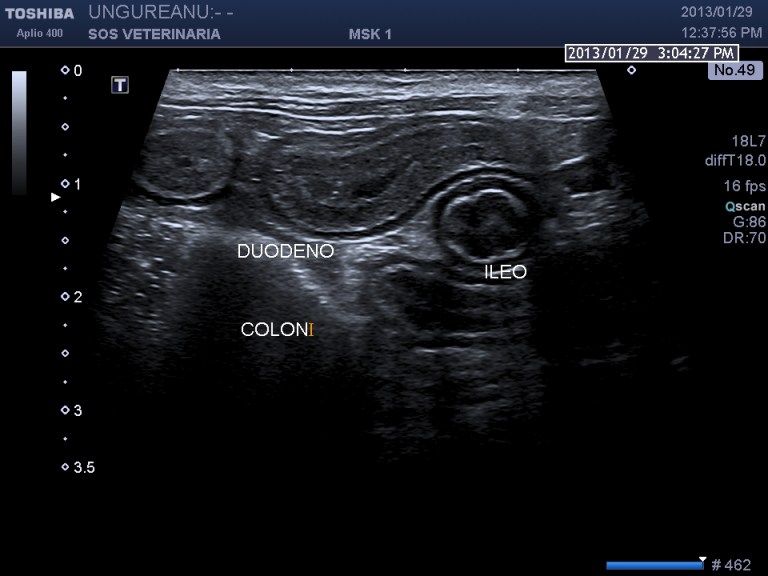

INFILTRAZIONE NEOPLASTICA PERITONEALE

Gatta comune europea di 14 aa

infiltrazione diffusa perironeale di immunoblasti ,ispessimento  mucosa intestinale-dilatazione coledoco -dotti pancreatici-calcolosi biliare intra epatica ed extraepatica

Rispetto il precedente caso la paipilla duodenale  e’ normale nella forma e nelle dimensioni ,sebbene affetto da calcolosi non si visualizzano calcoli nel coledoco o a livello della papilla che giustifichino la dilatazione delle vie biliari extraepatiche e pancreatiche  ,colpisce l’ispessimento del duodeno (5 mm contro un v.n. di 2,5 )  l’ectasia del dotto pancreatico, la stasi del succo pancreatico  e la diffusa presenza di strutture nodulari isolate o confluenti riferibili tessuto linfatico iperplastico  con un infiltrato di immunoblasti predominante .

dilatazione del coledoco che decorre rettilineo

dotto biliare e vena porta dotto pancreatico ectasico  duodeno